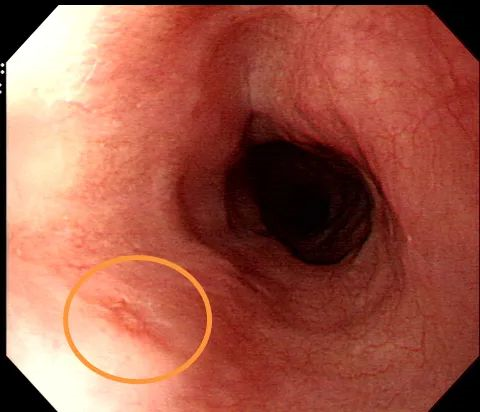

据患者自诉,因近日又出现反酸、胸部不适等症状,为求诊治从泸定县百里赴蓉城,慕名来到成都东大肛肠医院进行第三次复查,在检查过程中发现其食管大小约0.5cm稍发红黏膜,怀疑食道早癌病变,在我院内镜中心专家的建议下做了食道癌筛查,最终病检确诊为:高级别上皮内瘤变(早期癌)。

食管白光观察